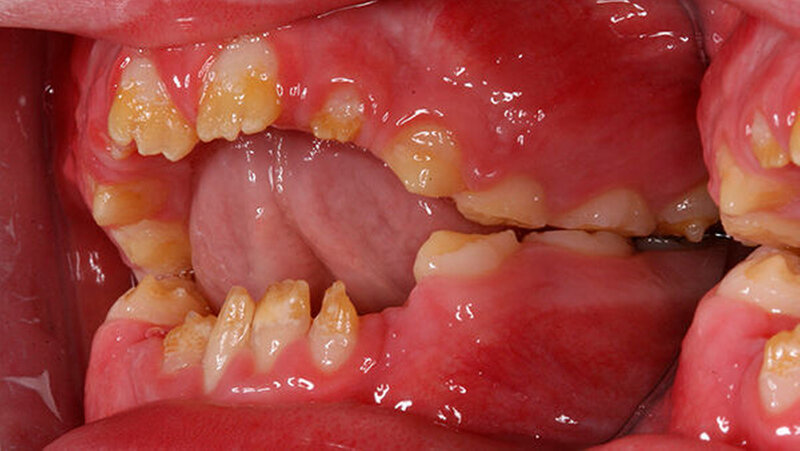

Der zehn Jahre alte Junge stellte sich an der Klinik wegen Schmerzen im ganzen Mund vor. Zusätzlich klagte der Patient über die eingeschränkte Möglichkeit Speisen ab zu beißen (Abbildung 1a und Abbildungen 3a und 3b). Die Familienanamnese ergab eine nahe verwandtschaftliche Verheiratung in der Familie. Das dentale Erscheinungsbild konnte von den Eltern des Patienten in der Verwandtschaft jedoch ausgeschlossen werden.

Der klinische Befund zeigte an beiden Dentitionen eine rauhe, zum Teil verminderte, bis fehlende Schmelzdicke und eine teilweise bräunliche Zahnverfärbung. Letztere wurden auch durch exogene Pigmenteinlagerung verursacht (Abbildung 1b und Abbildung 2).